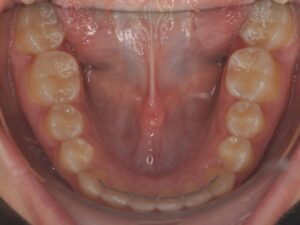

- d’un fil collé sur la face interne (linguale) des dents

- de gouttières passives de stabilisation réalisées sur mesure. `